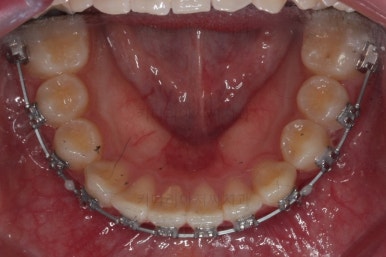

마찬가지로 부산교정치과 키다리아저씨치과에 처음 내원하셨을 당시의 입안 모습입니다.

화살표로 표시된 치아가 작은 앞니 부분인데 크기가 매우 작고 뾰족한 것을 볼 수 있어요. 유치가 아니고 평생 써야 하는 영구치입니다. 이러한 상태를 "왜소치"라고 표현하는데, 치아 크기의 문제로 여러 가지 문제점이 생길 수 있어요.

또 다른 문제는 위아래 앞니가 매우 많이 겹쳐져 있어서 아래 앞니가 거의 보이지 않는다는 점입니다.

처음 장치를 부착한 이 후 8개월이 흐른 시점이네요. 꽤나 오랫동안 천천히 송곳니를 가지런하게 해줘요.

치료 10개월째의 모습입니다.

이정도면 다 끝난 것 같은 느낌이 드시지 않나요? 과개교합도 개선시켰고 매복치아 덧니도 가지런하게 했어요.

작은 앞니가 왜소치이다 보니 윗니에는 틈이 남아있고 교합도 조금 엉성한 모습이에요.

왜소치의 사이즈가 위아래 교합을 맞춰주는데 방해가 된다고 판단하여 왜소치를 크게 해주기로 결정했습니다.